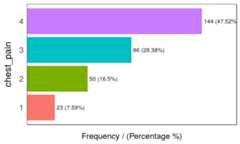

freq(data=heart_disease,input =c('thal','chest_pain'))

Figure 1.2: Frequency analysis 1

## thal frequency percentage cumulative_perc## 1 3 166 54.79 54.79## 2 7 117 38.61 93.40## 3 6 18 5.94 99.34## 4 <NA> 2 0.66 100.00

Figure 1.2: Frequency analysis 2

## chest_pain frequency percentage cumulative_perc## 1 4 144 47.52 47.52## 2 3 86 28.38 75.90## 3 2 50 16.50 92.40## 4 1 23 7.59 100.00## [1] "Variables processed: thal, chest_pain"As well as in the remainingfunModeling functions, ifinput is missing, then it will run for all factor or character variables present in a given data frame: